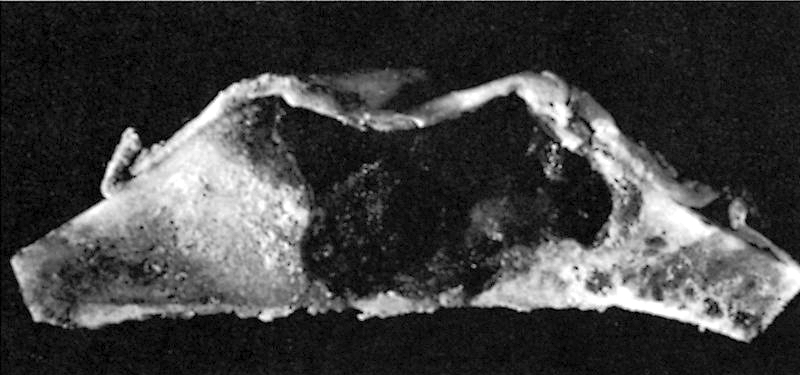

Gross description

- Well circumscribed lesion with a sclerotic rim centered within the cortex

- Cortex may be thinned as lesion expands

- Lesion itself may undergo aneurysmal bone cyst-like changes or cartilaginous metaplasia (Dorfman and Czerniak: Bone Tumors, 2nd Edition, 2015)

Gross images